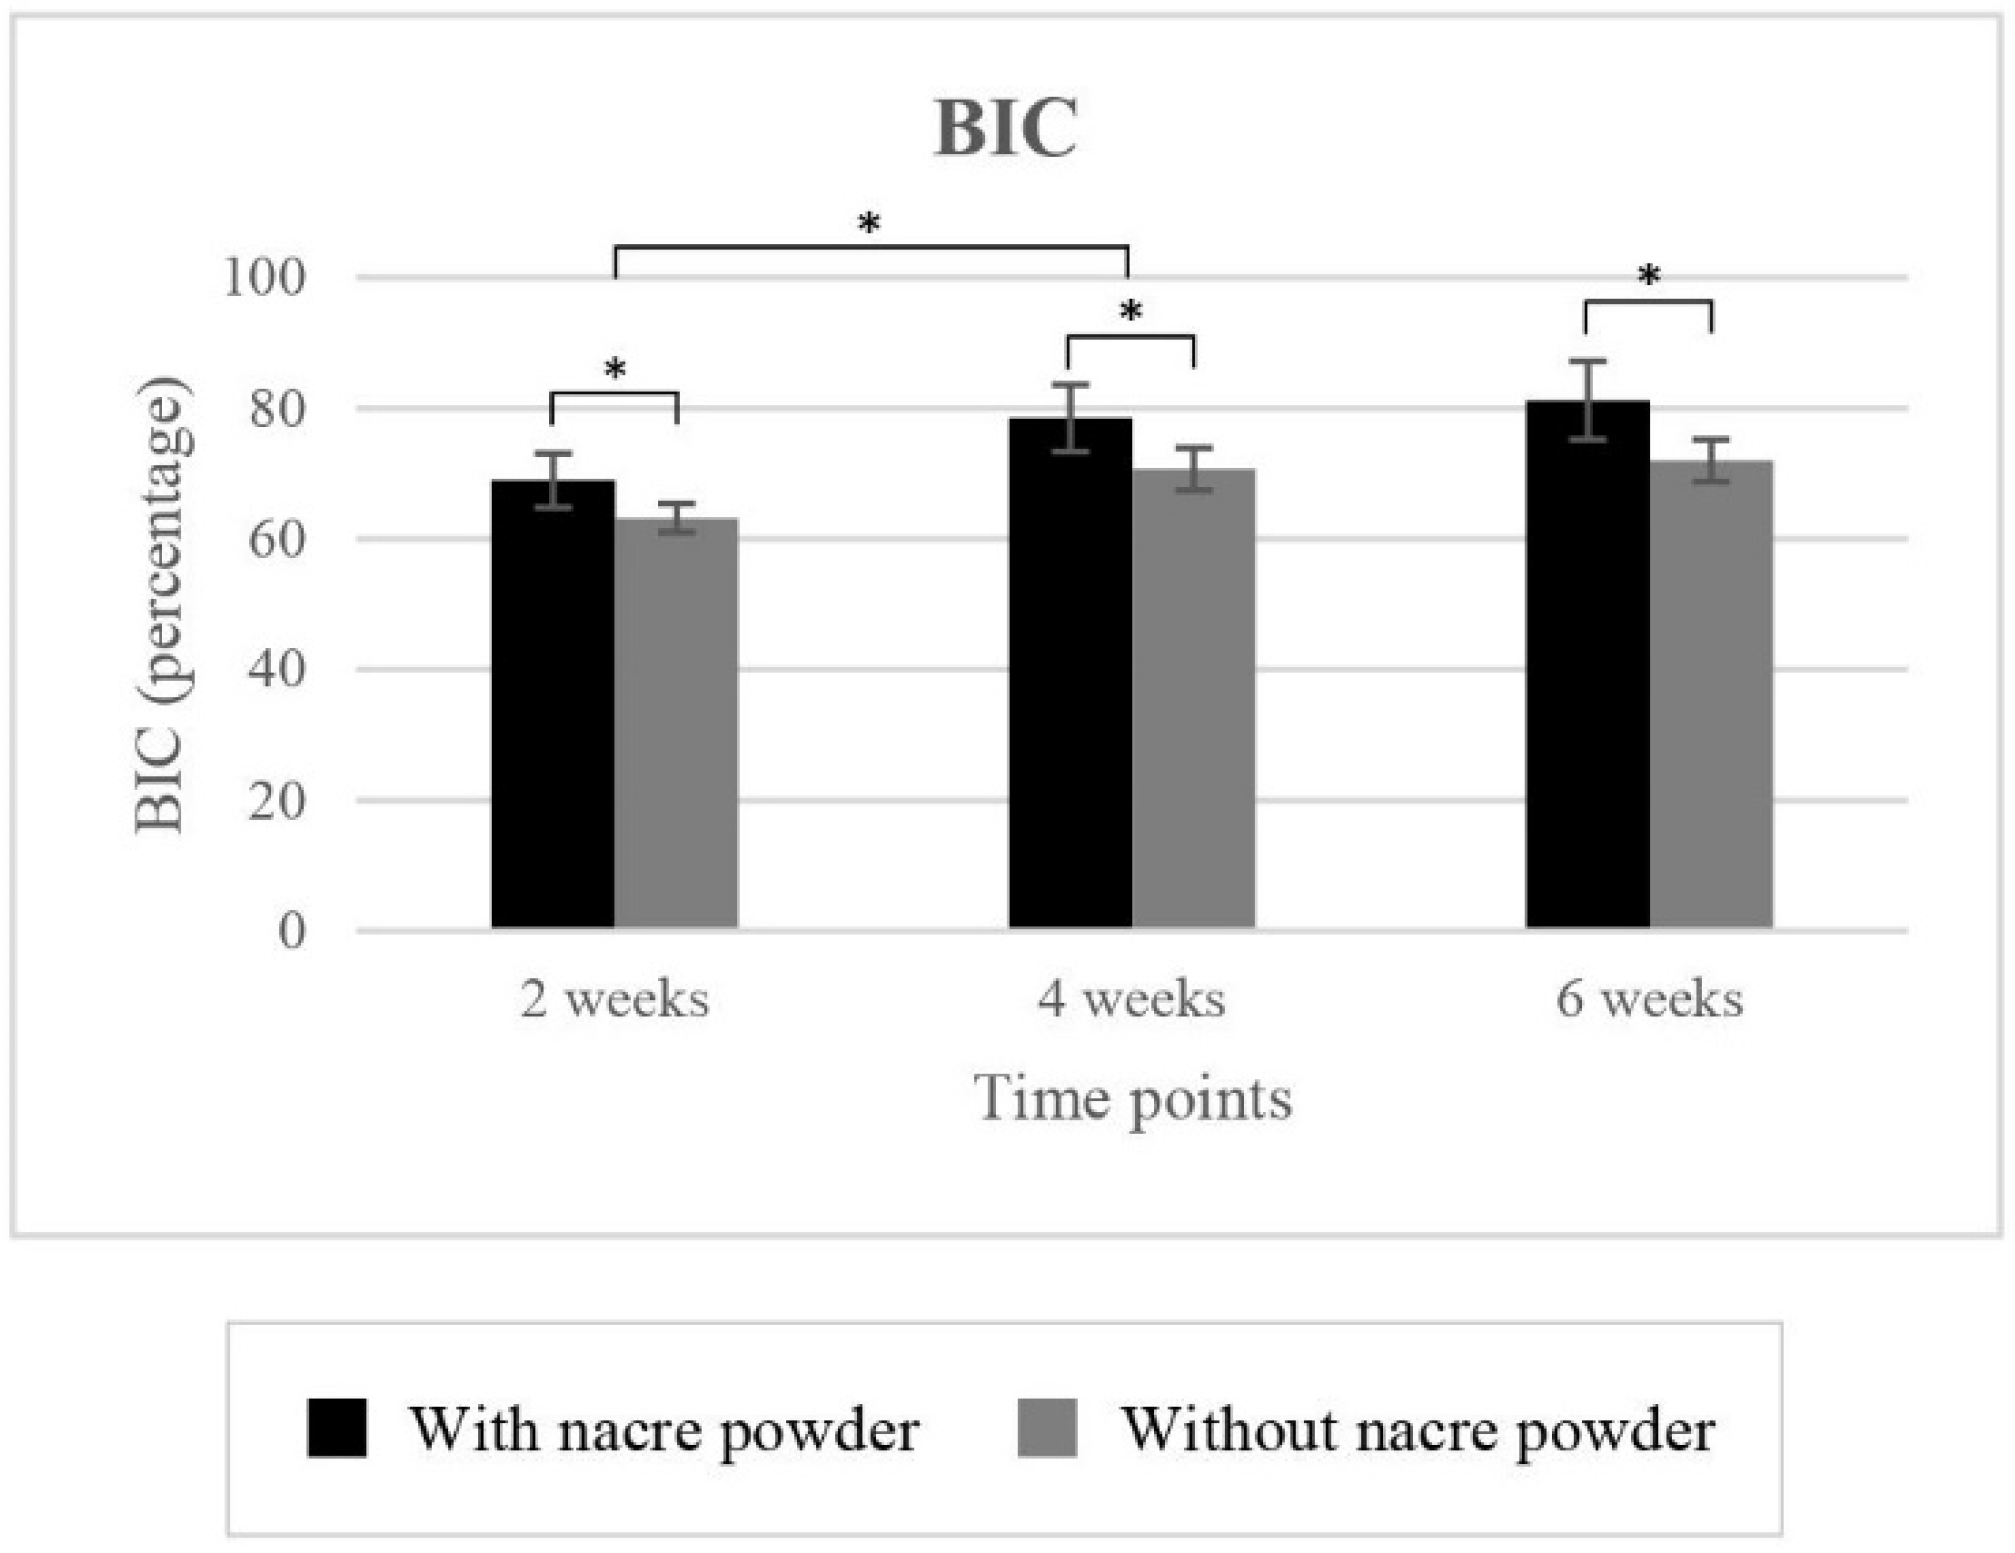

2.2.1. Bone-to-Implant Contact (BIC)

| Treatment | |||||||

|---|---|---|---|---|---|---|---|

| Without Nacre Powder (Controls) | With Nacre Powder | ||||||

| Time Points | 2 Weeks | 4 Weeks | 6 Weeks | 2 Weeks | 4 Weeks | 6 Weeks | |

| BIC (%) | |||||||

| 63.20 ± 2.20 | 70.67 ± 3.23 | 71.99 ± 3.24 | 68.99 ± 4.13 | 78.47 ± 5.15 | 81.19 ± 5.96 | ||